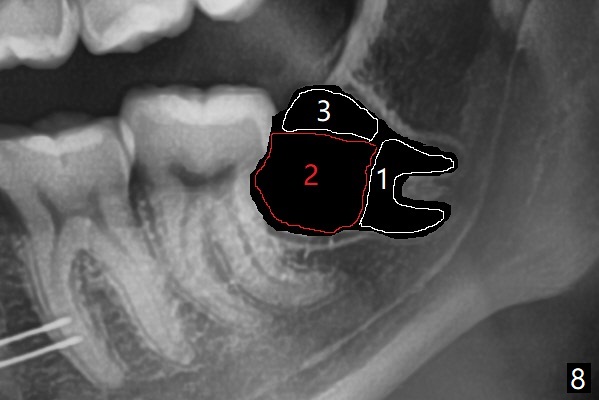

18岁女要求上大学前拔除智齿(图二),十三岁上四已经为了矫正而拔除(图一),所以现在只需要拔除下八,后者接近水平阻生,冠部可能位于下七远中颊侧(图三,四 *),所以附加切口应在七近中(红线)。智齿拔除后根部有两个牙槽窝(图五,六 *)。在右侧,塞入两个胶原塞(图七:1,2,collagen plug),其中一个末端剪开塞入根部牙槽窝。而左侧,使用一个胶原塞,但事先剪成两半(图八:1,3),第一部分也剪成燕尾,插入根部牙槽窝(1),然后在七远中放置骨水泥(1 cc Bond Apatite,2 红色),在后者上面放入胶原塞另外一半(3)。最后两侧都使用4-0 PGA 缝线。

使用胶原塞目的是预防干槽症,以前病例显示它促进骨化中心形成。骨水泥是一种医用性石膏(Biphasic Calcium Sulphate 硫酸钙 ),容易被身体吸收,3个月转换成自体骨。她哥哥(19岁)病例显示骨水泥与Osteogen Plug同样五个月会形成骨质。以后年轻人(25岁以下)智齿拔除不必植骨或者放置骨水泥。左下,右下智齿的确位于第二磨牙颊侧,事先附加切口近中,缝合后伤口不易裂开,骨粉丢失。拔除后即刻拍摄根尖片(图九,十),目的建立原有解剖,与愈合后比较,意外发现断裂牙片(F),后来取出。